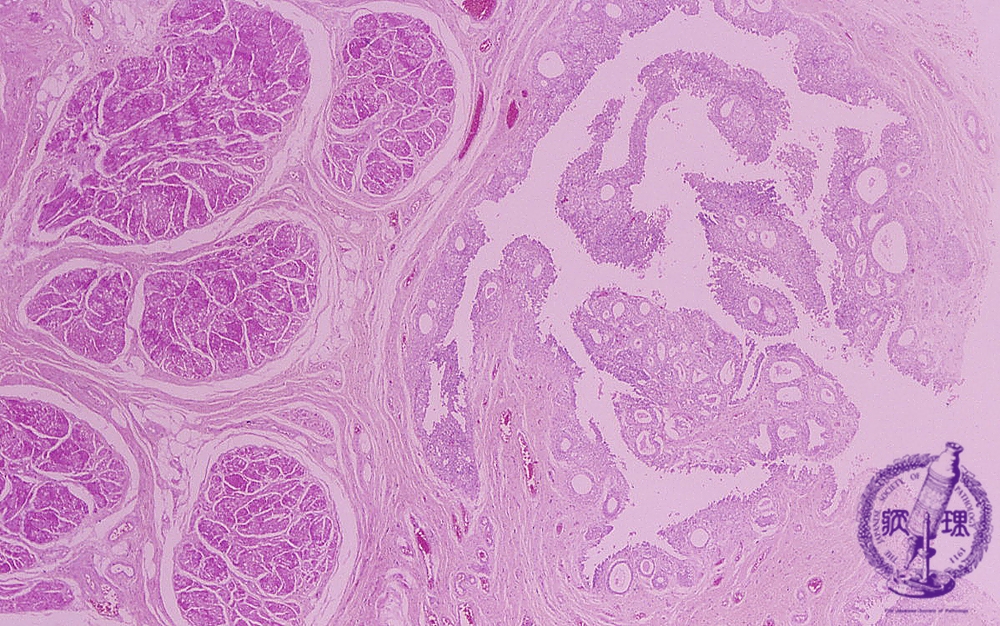

Microscopic findings (HE, high power view): Cystitis cystica. The von Brunn’s nests are dilated to form cystic lesions (yellow arrows).

Click the image to see the enlarged image.